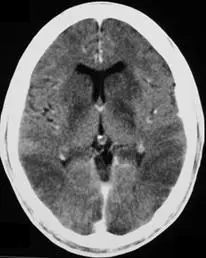

50歲女性患者,近期因急性心臟衰竭而昏迷,接受電腦斷層檢查,圖為注射顯影劑後的影像,下列何者是最可能的診斷? 圖片描述

從影像可見:

1. 兩側大腦半球瀰漫性低密度,灰白質分界模糊。

2. 皮質下白質密度相對較高,形成逆轉(reversal)或 white cerebellum sign 的前驅表現。

3. 腦回變平、腦溝消失,側腦室輕度受壓,符合廣泛性腦水腫。

4. 基底核與皮質同樣變得低密度,強化「全球性低血氧」而非局灶病變的印象。

上述變化為成人 HIE 在非增強/增強 CT 上最典型的早期表徵,與單一葉或特定核團受累之病因(如病毒性腦炎、Wernicke’s 或 hepatic encephalopathy)明顯不同。 (medicine.uams.edu, pmc.ncbi.nlm.nih.gov, radiopaedia.org)

心肺衰竭後的全球缺氧可於數小時內在 CT 看到:灰白質分界消失、基底核低密度、腦溝/腦室受壓,嚴重時呈 white cerebellum sign。與題目影像及臨床背景(急性心衰竭昏迷)完全符合,故為最可能診斷。 (medicine.uams.edu, pmc.ncbi.nlm.nih.gov, radiopaedia.org)

該患者因急性心臟衰竭導致全身灌流壓急劇下降,全球性腦缺氧缺血。CT 顯示典型 HIE 表現:瀰漫性低密度、灰白質分界消失、基底核與皮質同時受累、腦溝及腦室受壓。其他選項之影像特徵皆無法解釋如此「對稱且廣泛」的低密度改變,故正確答案為 D 缺氧缺血性腦病變。